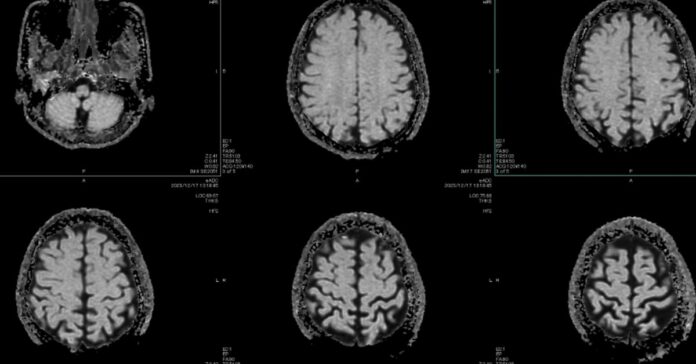

Artificial intelligence (AI) has profound implications for healthcare, facing intense challenges like regulation and ethical considerations. Geoffrey Hinton, often referred to as the “Godfather of AI,” predicted AI would replace radiologists, yet the opposite has occurred, with demand for human expertise growing alongside AI advancements. Hinton emphasizes that AI won’t replace healthcare workers; instead, it will reveal unmet medical needs. Notably, AI has outperformed some physicians but struggles with reliability in complex diagnoses. The potential of AI lies not just in enhancing diagnostics, but in shifting towards preventive medicine, leveraging data from wearables and biomarker analysis. However, legal and ethical barriers pose challenges, such as liability concerns when AI errors occur. Empathy remains a critical aspect of healthcare that machines can mimic but not replicate. In essence, the future of healthcare AI is about collaboration, improving patient outcomes, and streamlining preventive care, rather than outright replacement of human practitioners.